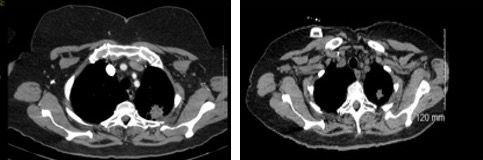

A 68-year-old Caucasian woman, lifelong nonsmoker, presented with recurring cough and upper respiratory infection symptoms. Despite initial improvement with antibiotics at each episode, the recurrent nature of her symptoms led to further work-up. A CT scan of her chest revealed a left apical pulmonary mass measuring up to 2.6 x 3.1 cm and a left aorticopulmonary window mediastinal lymph node measuring 2.7 x 3.0 cm (Figure 1). CT-guided biopsy of the lung lesion revealed an adenocarcinoma consistent with lung primary. Further work up with a PET-CT scan confirmed the left apex lung mass with a maximum standardized uptake value (SUV) of 6.4 and the left aorticopulmonary window lymph node with a maximum SUV of 6.7. There were no other hypermetabolic areas. She was staged as cT2cN2cM0, stage IIIA.

Figure 1. CT scan through the lung apices shows a 3.1cm spiculated mass with central low density consistent with necrosis. At the level of the left upper aorticopulmonary window region, there is a 3cm nodal soft tissue mass with central density consistent with necrosis.

Figure 2. CT scan after treatment shows significant reduction of the left apical pulmonary mass and the left upper hilar nodal mass, consistent with a positive response to chemoradiation.